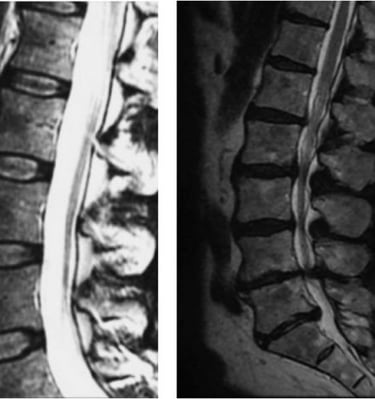

Galeria

Imagens detalhadas para entender melhor cada condição.